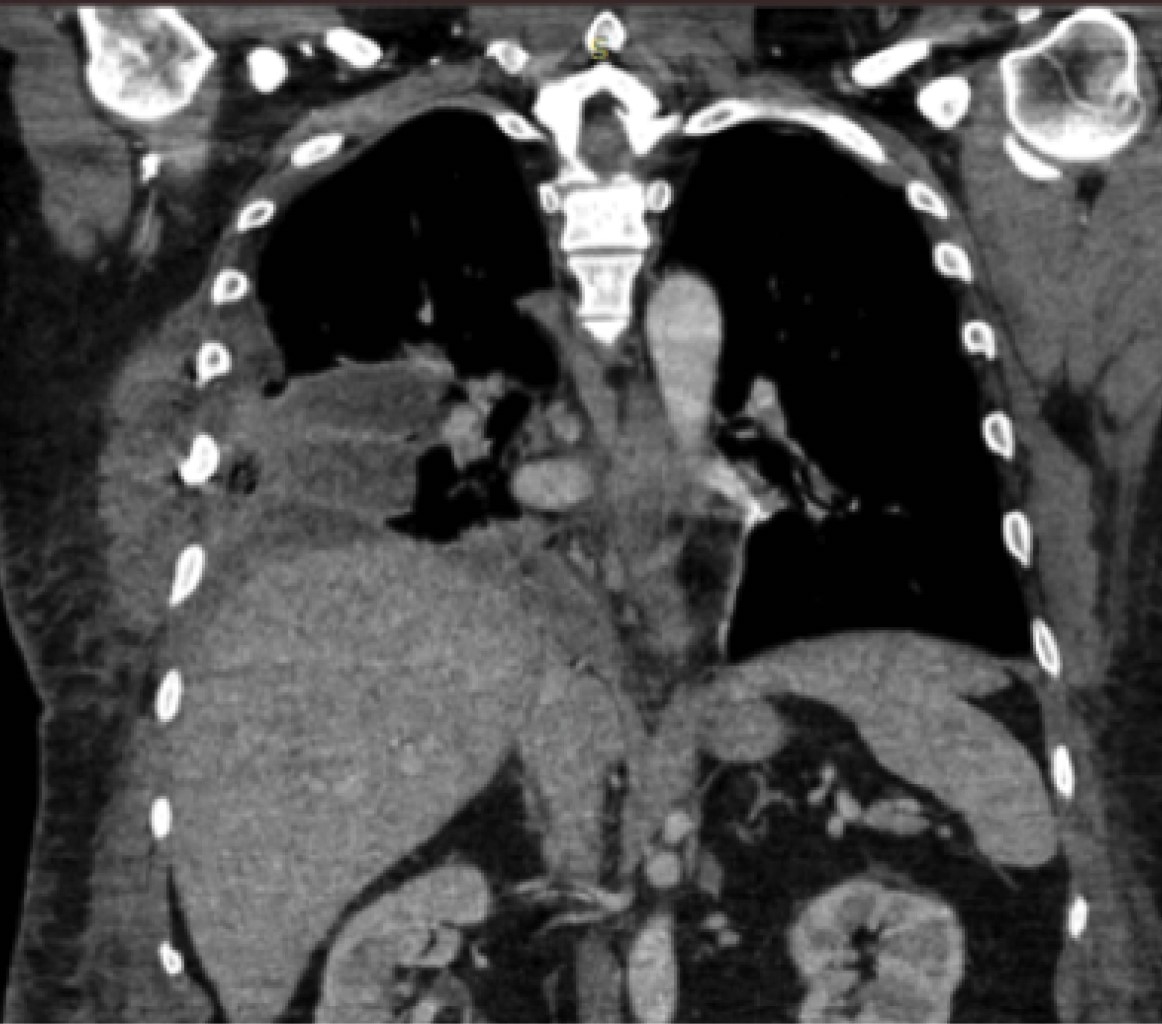

Estudios de laboratorio normales, exceptuando leucocitos: 14.2 mil/mm³, CPK 2,948 μmol/L. Se realiza radiografía de tórax (Figura 1) y tomografía computarizada (TC) toraco-abdominal (Figura 2, 3 y 4) observando neumotórax derecho de 30%, fracturas costales bilaterales de segunda a la séptima. En ambos estudios no se evidencia la presencia de hernia diafragmática.

Se debe tener un alto nivel de sospecha clínica, ya que los hallazgos por imagen frecuentemente son poco específicos. El diagnóstico de la ruptura diafragmática puede obviarse hasta en 66% de los pacientes, dada la dificultad para el mismo al asociarse a otras lesiones diafragmáticas.7 La prevalencia de signos positivos en radiografía de tórax varía entre 3-89% de los casos2 y puede mostrar nivel hidroaéreo intratorácico o la localización intratorácica de la sonda nasogástrica. La elevación de una cúpula diafragmática en ausencia de atelectasias homolaterales y el contorno borroso del diafragma son datos inespecíficos y son difíciles de interpretar en el paciente traumatizado.2 La radiografía de tórax conduce al diagnóstico únicamente en 62% de los pacientes.

Figura 1